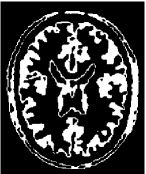

4.2 Inhomogeneous image segmentation

In this subsection, we extend our proposed method to segment two classes of inhomogeneous images shown in Figure 4.6. The left is a synthesized image by combining the arterial blood vessels of a human head. The right is a MRI brain image based on an anatomical model of normal brain from the slice 91 of the normal brain database, which is available to the public at http://www.bic.mni.mcgill.ca/brainweb/. Here we set as “modality=T1, Slice thickness=1mm, intensity non-uniformity = 20%” for the original image 4.6(b). Different to the numerical comparisons of the piecewise constant image, we do not know the real segmentation due to the inhomogeneity. So we except to obtain a better restored image as the stopping condition in the first step of our proposed strategy.

Refer to caption

(a) Synthesis Image

(b) MRI Image

Figure 4.6: The original images in Example 4.3 and 4.4.